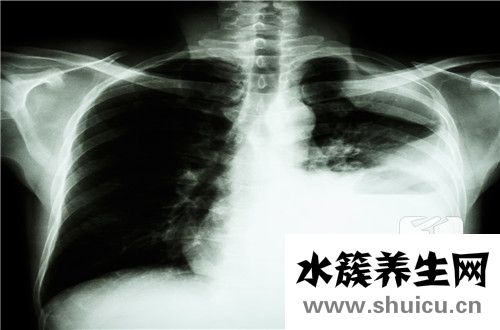

肺健康對人體非常重要,因為肺是呼吸循環的中心,人必須通過肺才能實現血液輸送氧氣的功能。盡管肺在體內占據了很大的體積,但它們很容易受到疾病的影響,并給人們帶來很多痛苦。例如,肺部炎癥是一種常見...